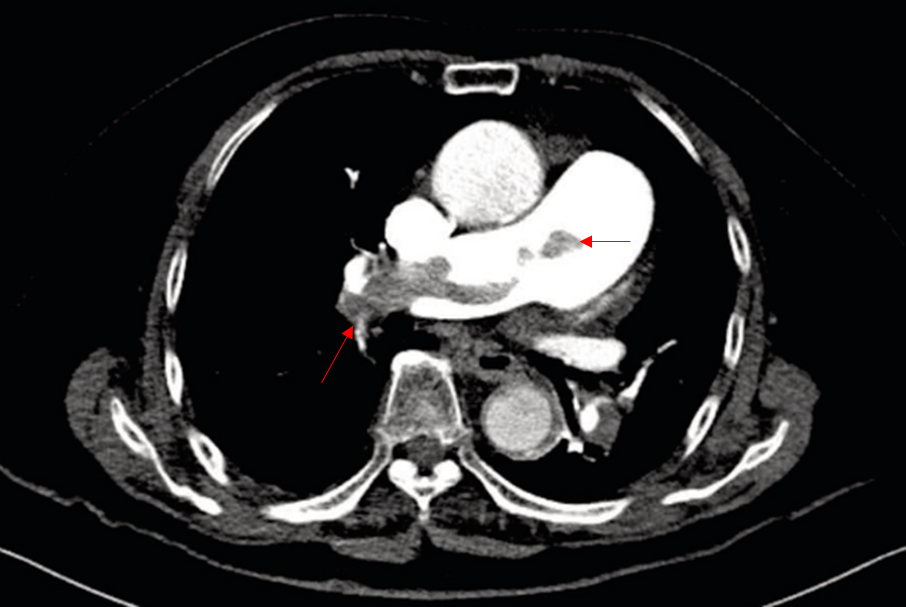

84세 여자가 1주 전부터 숨이 찬다며 응급실에 왔다. 한 달 전 등뼈 골절 이후 거의 누워 지냈다고 한다. 혈압 110/56 mmHg, 맥박 110회/분, 호흡 20회/분, 체온 36.5℃ 이다. 가슴청진에서 심음은 빠르고 규칙적이며 심잡음은 들리지 않는다. 혈액검사 결과는 다음과 같다. 가슴 컴퓨터단층촬영 사진이다. 치료는?

Img | CT: Filling defect at Rt. main pulmonary artery |

• PTE 진단을 위해 CT를 시행, Rt. main pulmonary artery에 매우 큰 thrombus가 확인된다. 따라서 PTE로 진단한다.

CT상 PTE가 확인되나 V/S stable하므로 anticoagulant인 heparin을 투여한다.

• PTE의 치료는 V/S stable할 경우 금기증이 없는 한 anticoagulant를 투여한다. 본 환자는 anticoagulant의 금기라고 볼 만한 요소가 확인되지 않으므로 우선 투여해야 한다. 보기 중 heparin이 이에 해당한다.